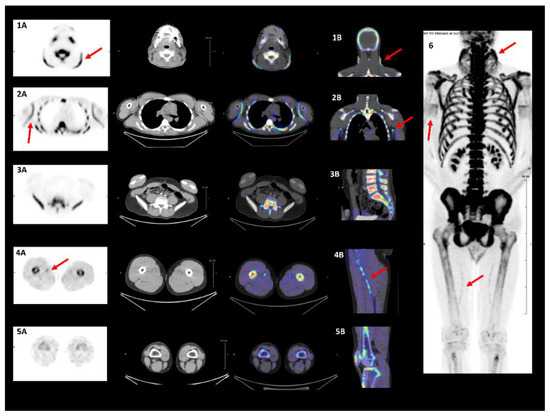

- Mention, P.; Lacoeuille, F.; Leftheriotis, G.; Martin, L.; Omarjee, L. 18F-flurodeoxyglucose and 18F-sodium fluoride positron emission tomography/computed tomography imaging of arterial and cutaneous alterations in pseudoxanthoma elasticum. Circ. Cardiovasc. Imaging 2018, 11, e007060. [Google Scholar] [CrossRef]

- Gutierrez-Cardo, A.; Lillo, E.; Murcia-Casas, B.; Carrillo-Linares, J.L.; García-Argüello, F.; Sánchez-Sánchez, P.; Rodriguez-Morata, A.; Aranda, I.B.; Sánchez-Chaparro, M.Á.; García-Fernández, M.; et al. Skin and arterial wall deposits of 18F-NaF and severity of disease in patients with pseudoxanthoma elasticum. J. Clin. Med. 2020, 9, 1393. [Google Scholar] [CrossRef]

- Oudkerk, S.F.; de Jong, P.A.; Blomberg, B.A.; Scholtens, A.M.; Mali, W.P.T.M.; Spiering, W. Whole-body visualization of ectopic bone formation of arteries and skin in pseudoxanthoma elasticum. JACC Cardiovasc. Imaging 2016, 9, 755–756. [Google Scholar] [CrossRef] [PubMed]